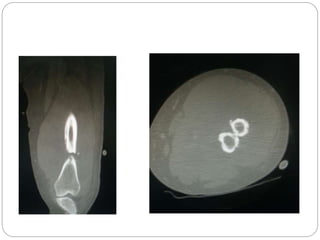

This document discusses 8 oncology cases. Case 1 involves a 40-year old female with right knee pain. Case 2 is a 28-year old male with a left subtrochantric fracture from a MVA who is now experiencing increasing left knee pain and swelling. Biopsy results showed high-grade osteosarcoma. Case 3 is a 30-year old female with breast cancer and bone metastases causing bilateral hip pain.